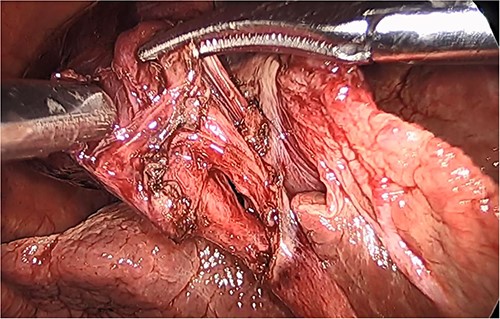

She had a good functional baseline, living in home independently and following anaesthetic review; after a family discussion, the consensus was to proceed to surgery. She underwent a laparoscopic cholecystectomy, and intraoperatively, the diagnosis of gallbladder volvulus was confirmed. A distended gangrenous gallbladder was found, which had undergone 360° clockwise rotation about the cystic duct (Figs 2, 3). The gallbladder was detorted to facilitate a traditional dissection of Calot’s triangle, achieving the critical view of safety (Figs 4, 5). The cystic duct was able to be cannulated facilitating an intraoperative cholangiogram which was unremarkable (Fig. 6). The gallbladder was then removed, and operation was completed without any complications. The histopathology of the gallbladder found diffuse haemorrhagic necrosis of the gallbladder without any evidence of dysplasia or malignancy. No cholelithiasis was present.

Intraoperative picture of the critical view following dissection of the cystic duct and artery.